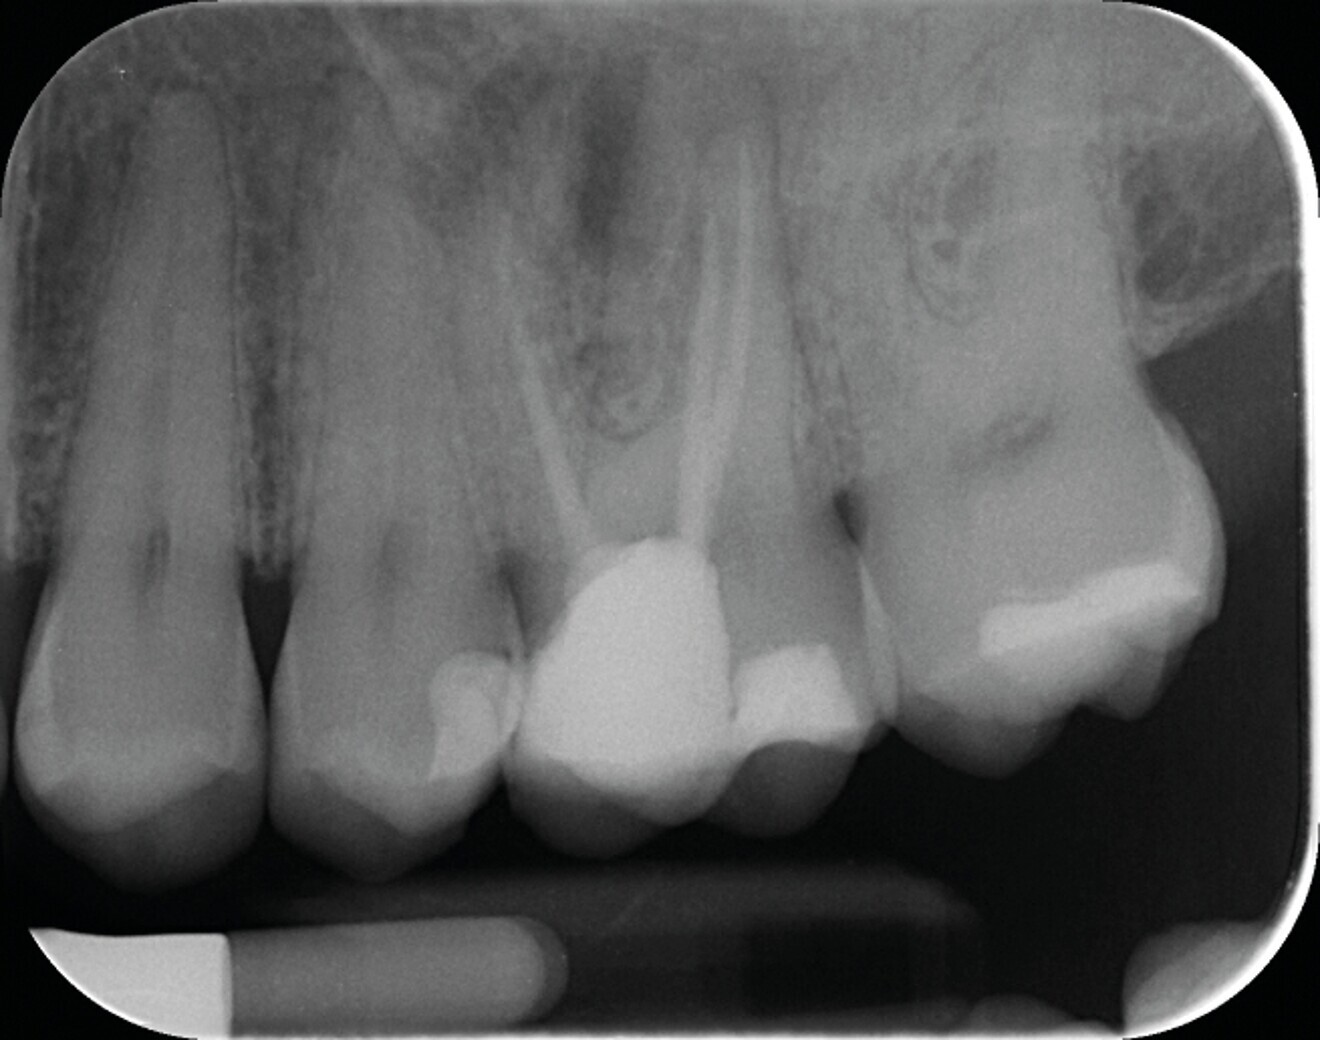

Avec la désinfection et l’obturation du système canalaire, nous ne faisons que rétablir un contexte biologique favorable à la cicatrisation parodontale et à la régénération osseuse (Figs. 1a–c).

Fig. 1a : Radiographie pré-opératoire d’une molaire maxillaire (16) présentant une lésion apicale sur la racine mésio vestibulaire. Le retraitement a consisté à éliminer le matériau présent dans les canaux, récupérer la perméabilité du canal de la racine MV et gérer la fausse route faite lors du traitement précédent.

Fig.1b : La radiographie post-opératoire objective une atteinte des objectifs techniques (obturation Bioroot RCS (Septodont).

Fig. 1c : La radiographie de contrôle à un an, confirme l’efficacité du traitement par la régénération osseuse.